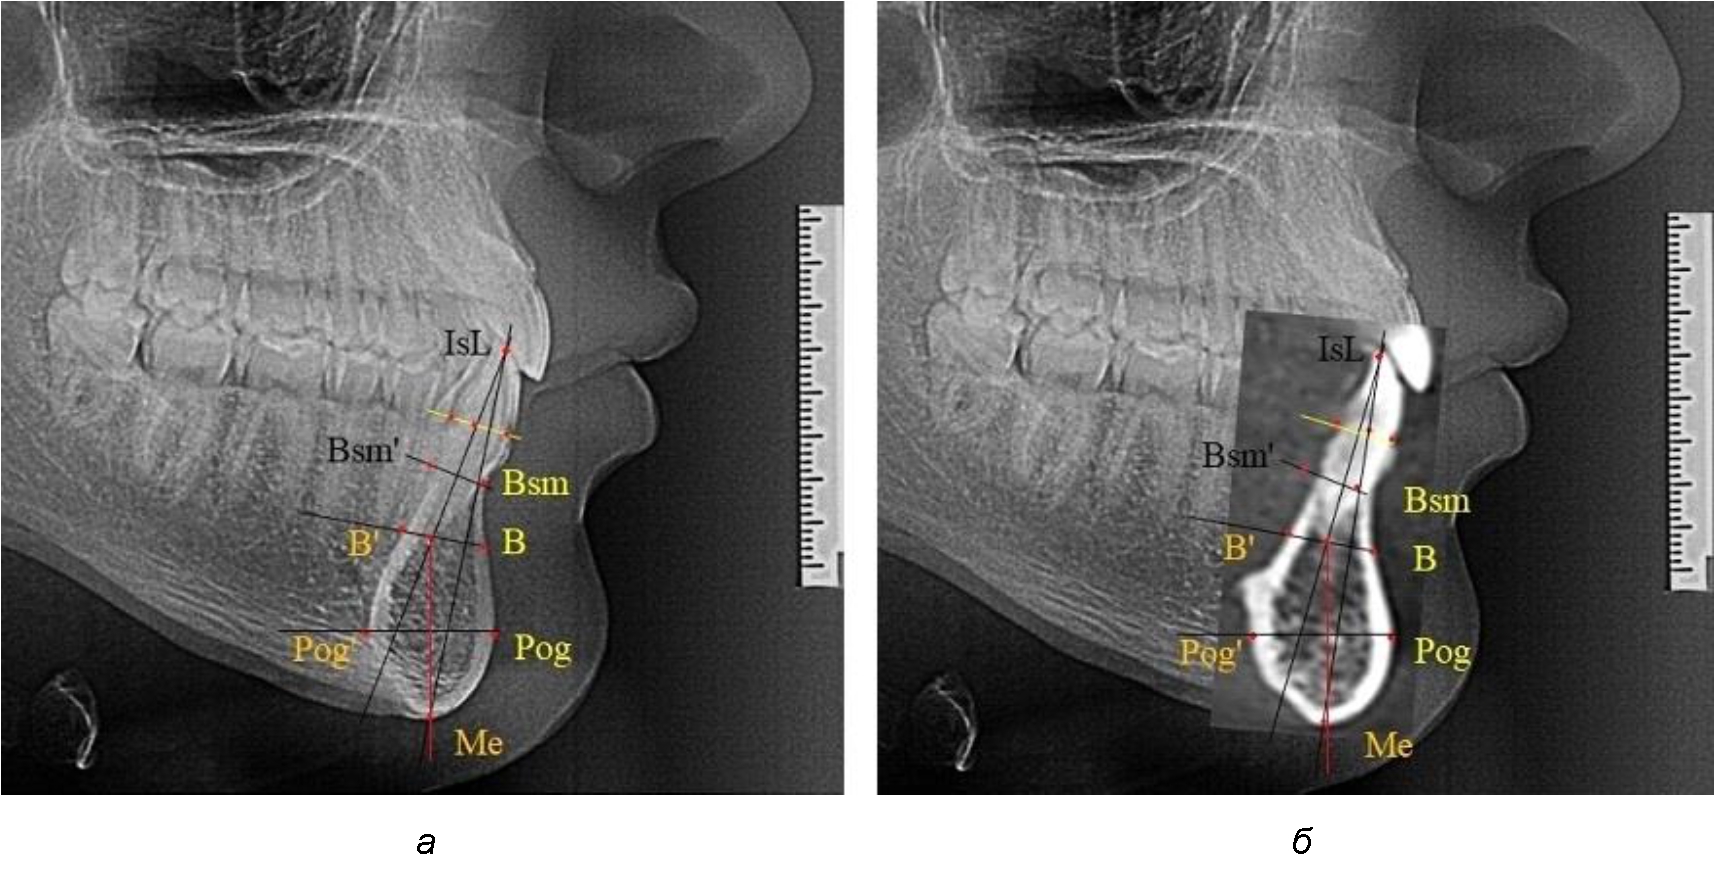

При анализе боковых телерентгенограмм использовали фрагменты гнатической части, на которых оценивали вертикальные и сагиттальные параметры резцового нижнечелюстного сегмента, на который наносили те же ориентиры, что и при анализе нативных препаратов и их рентгенограмм.

При необходимости и/или возможности проведения КЛКТ-исследования проводили анализ с сопоставлением фрагмента, что повышало точность диагностических мероприятий (рис. 2).

Рис. 2. Фрагменты ТРГ с ориентирами для измерения параметров резцового сегмента (а) и с наложением фрагмента КЛКТ (б)

Варианты резцовых сегментов нижней челюсти различные как по ширине, так и по высоте, а также по расхождению положения апикальных точек по Downs и Schwarz представлены на рис. 4.

Рис. 4. Особенности нижнечелюстного резцового сегмента на ТРГ у людей при среднем (а), широком (б) и узком (в) вариантах